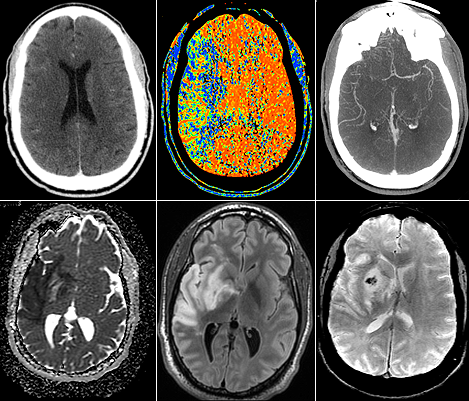

La neuroradiologie est une sous-spécialité de la radiologie, spécialisée dans l'imagerie diagnostique du cerveau, de la colonne vertébrale, de la tête et du cou.

Les neuroradiologues ont une formation en radiologie diagnostique pour étudier diverses maladies telles que les accidents vasculaires cérébraux, les maladies démyélinisantes, les maladies neurodégénératives, les tumeurs cérébrales, les cancers de la tête et du cou, les maladies neurovasculaires, les traumatismes, les douleurs dorsales et d'autres maladies neurologiques.

Les principales modalités d'imagerie sont la tomodensitométrie (Scanner) et l'imagerie par résonance magnétique (IRM).